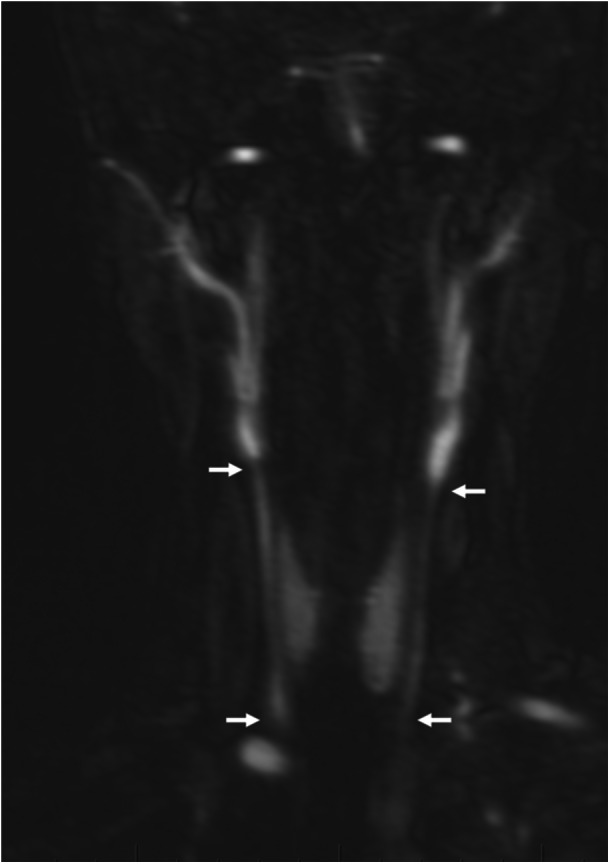

Extraintestinal manifestations in inflammatory bowel disease (IBD) most frequently involve the joints, skin, and organs such as the liver and pancreas. Inflammation of the aorta is less commonly described in pediatrics, although it has been described in adults. We report a case of an adolescent female with Crohn's disease who presented with worsening diarrhea, vomiting, and weight loss, found to have aortitis on imaging. We review the pathogenesis and clinical features of Takayasu arteritis, as well as some of its similarities to IBD to raise awareness, as early detection of this less-known extraintestinal manifestation has been associated with better outcomes.

炎症性肠病(IBD)的肠外表现最常涉及关节、皮肤和器官,如肝脏和胰腺。主动脉炎症在儿科中不太常见,尽管在成人中有过描述。我们报告一个患有克罗恩病的青春期女性的病例,她表现为腹泻、呕吐和体重减轻,影像学检查发现她患有大动脉炎。我们回顾了Takayasu动脉炎的发病机制和临床特征,以及它与IBD的一些相似之处,以提高人们的认识,因为早期发现这种鲜为人知的肠外表现与更好的结果相关。